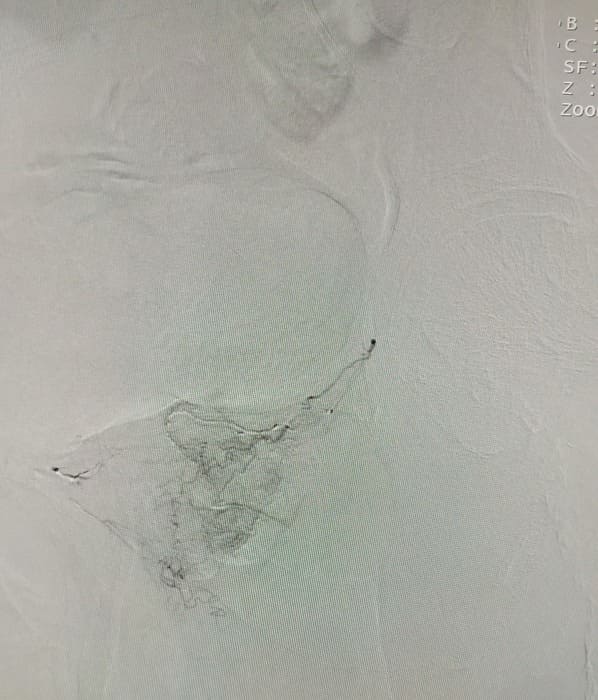

Зазвичай люди літнього віку мають вражені атеросклерозом та звивисті, внаслідок гіпертонічної хвороби судини. Цей випадок не був виключенням, тому нам довелося докласти максимум зусиль, використати високотехнологічне обладнання та інструменти, щоб віднайти цільові судини. На диво, незважаючи на попередню операцію, судинний малюнок рецидивної простати збігався з тим який буває у не оперованих пацієнтів. Тому нам вдалося їх чітко визначити з обох сторін та заповнити емболами. Це доволі кропітка праця, адже щоб викликати ішемію, необхідно поступово виключити кровоплин в усій тканині залози. Полегшувало операцію лише відсутність перетоків артерій на сусідні органи. Це дозволило нам безпечно емболізувати, не боячись негативних наслідків та ускладненнь.